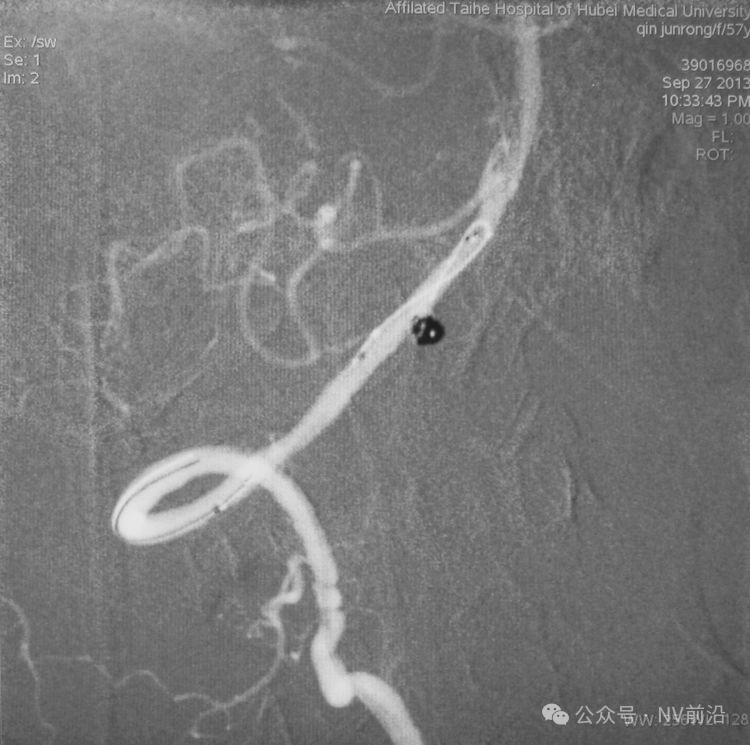

Solitaire 4×15支架(绿线)跨瘤颈半释放,压住微导管(红线)。

经微导管向瘤腔内送入首枚弹簧圈(QC-2-4-3D)。

继续送入两枚QC-1.5-2-Helix,完全栓塞动脉瘤,部分圈突入载瘤动脉。